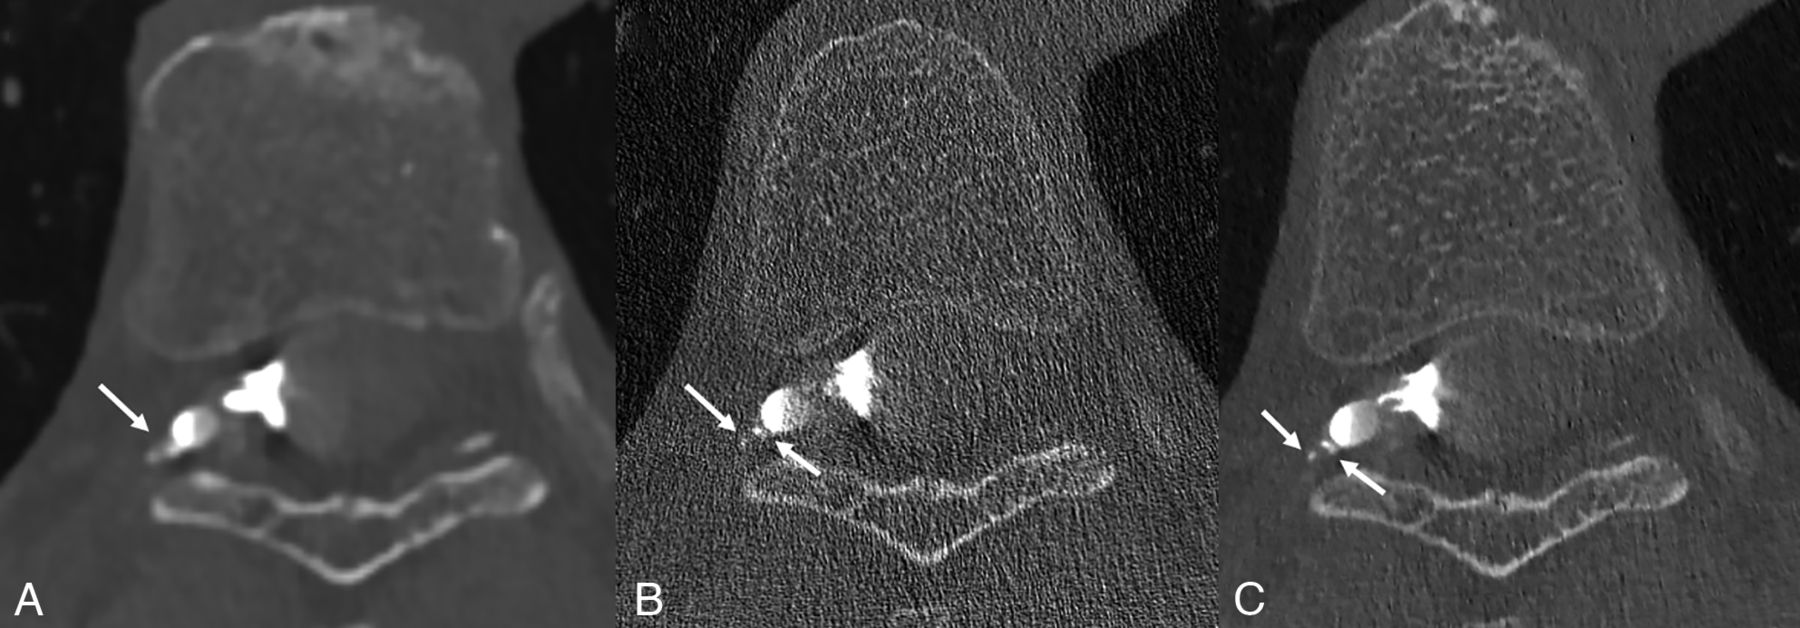

Axial low-energy thresholded (T3D) images in a 70-year-old woman with a right T7 CVF. Images were reconstructed using a Br56 kernel (A), a sharper Qr89 kernel (B), and a Qr89 kernel after denoising with the trained model (C), all presented at the same section and window/level settings. The Br56 kernel demonstrates ill-defined contrast lateral to a right T7 diverticulum (A, arrow), which was thought to be suspicious but not definitive for a CVF. The Qr89 kernel more clearly delineates this finding as likely venous opacification (B, arrows), though substantial noise degrades the overall image quality and results in uncertainty in the findings. The denoised Qr89 image clearly characterizes these structures as tiny veins, (C, arrows), confirming the presence of a CVF.